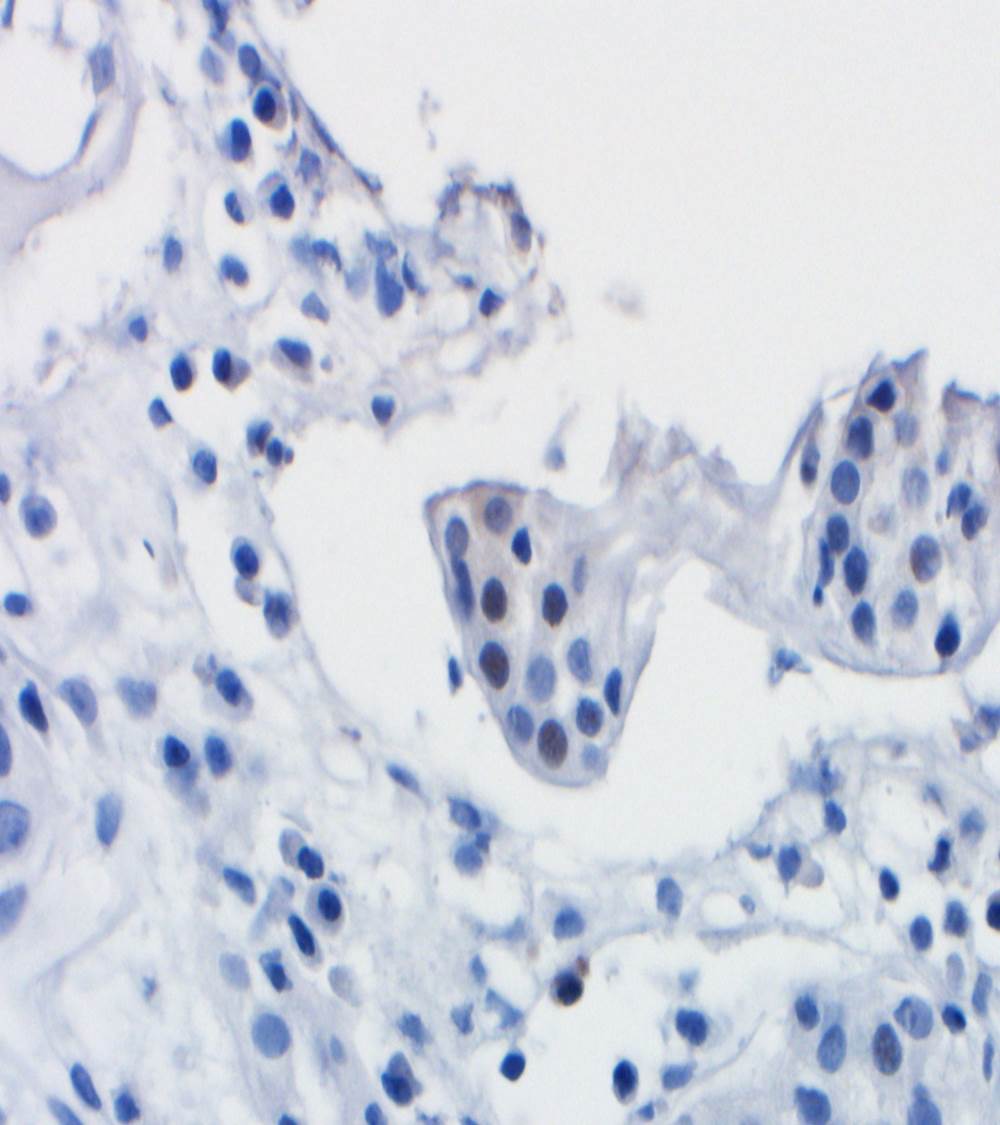

A renal allograft biopsy is essential to differentiate adenoviral nephritis from that of acute rejection or other pathology. Typical light microscopic findings in adenovirus nephropathy include tubular cell necrosis (with tubular basement membrane rupture) associated with severe interstitial inflammation (sometimes with granuloma formation), focal interstitial hemorrhage and viral cytopathic changes including peripheral condensed chromatin, basophilic nuclear inclusions and nuclear enlargement. In some cases such as ours, viral inclusions are not identified, presumably because of the focal nature of viral infection in the kidney. Immunoperoxidase staining can be used to confirm the presence of adenovirus within the nuclei, and to a lesser degree, within the cytoplasm of tubular epithelial cells; although weak, our case showed positive staining. These viral particles are visible under electron microscopy, measuring approximately 75 nm, however they were absent in our patient. Diagnosis in such cases can be clinched by urine examination showing white cell casts and decoy cells, and PCR on the urine testing positive for viral DNA.